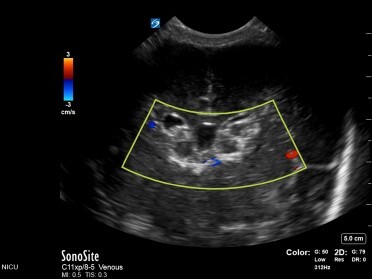

Neonatology Evolving Hydrocephalus Image